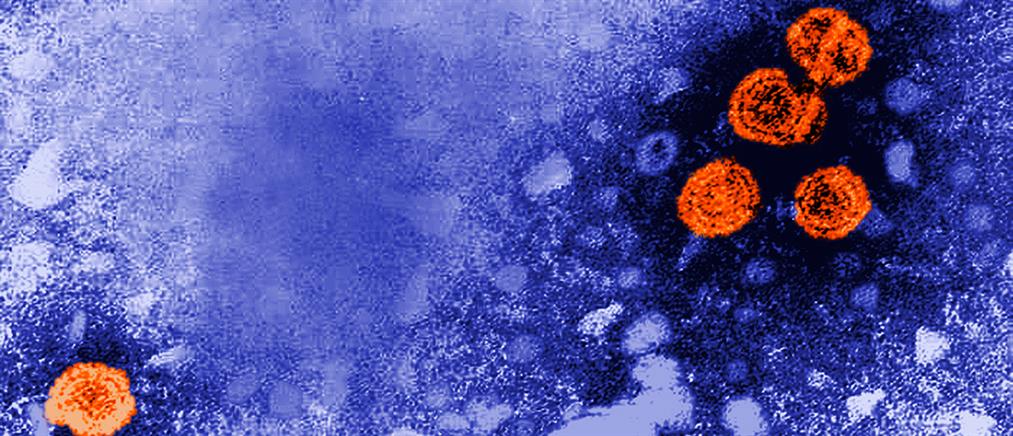

Παγκόσμια ημέρα Ιογενούς Ηπατίτιδας: Μάθε την αλήθεια - Εξετάσου!

Στρατηγικός στόχος του Παγκόσμιου Οργανισμού Υγείας είναι η εξάλειψη της ιογενούς ηπατίτιδας Β και C μέχρι το έτος 2030.